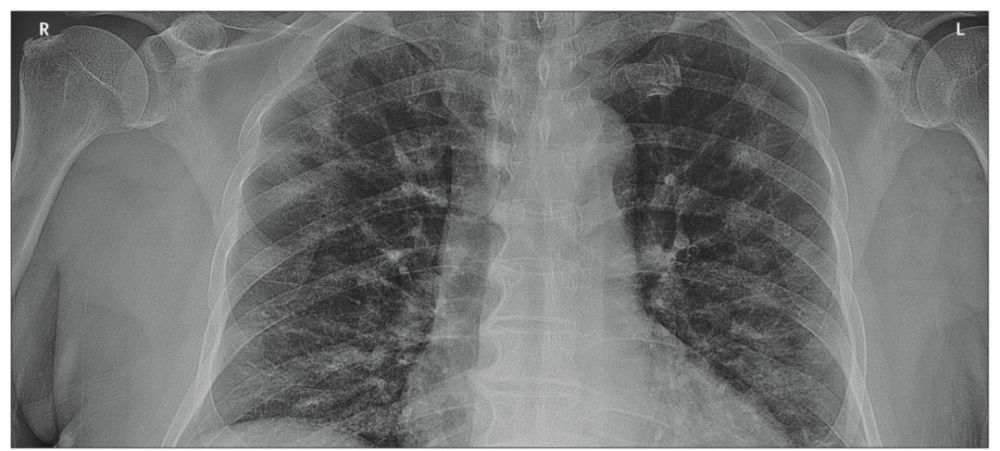

负责治疗首例患者的医院团队对病例进行了详细分析,发表在柳叶刀上的论文《加拿大首例新冠病毒病例,表现为轻度肺炎》显示患者在早期的检查中,除了出现血小板计数减少的症状以外,大多数血液指标都在正常范围内;最具有提示性意义的是胸部X片的扫描,出现了斑片状,双侧支气管血管周围都呈现出模糊不清的混浊状。

文章记录,尽管影像学结果有显著异常,但是该患者的状况依旧良好,甚至不需要做插管和补充氧气的治疗,他们认为这点和其它地方所报道出的具有类似X光结果的病例有所不同。